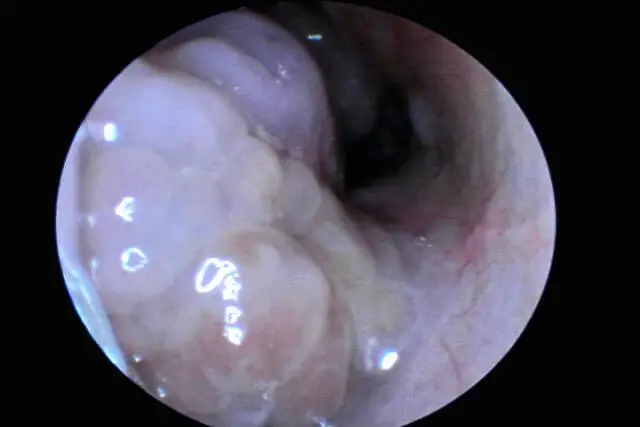

粘液性息肉:最常见,外观类似剥皮葡萄或鲜荔枝肉,表面光滑半透明、呈粉红色,带有细蒂,触感柔软可活动,多生长在中鼻道内;